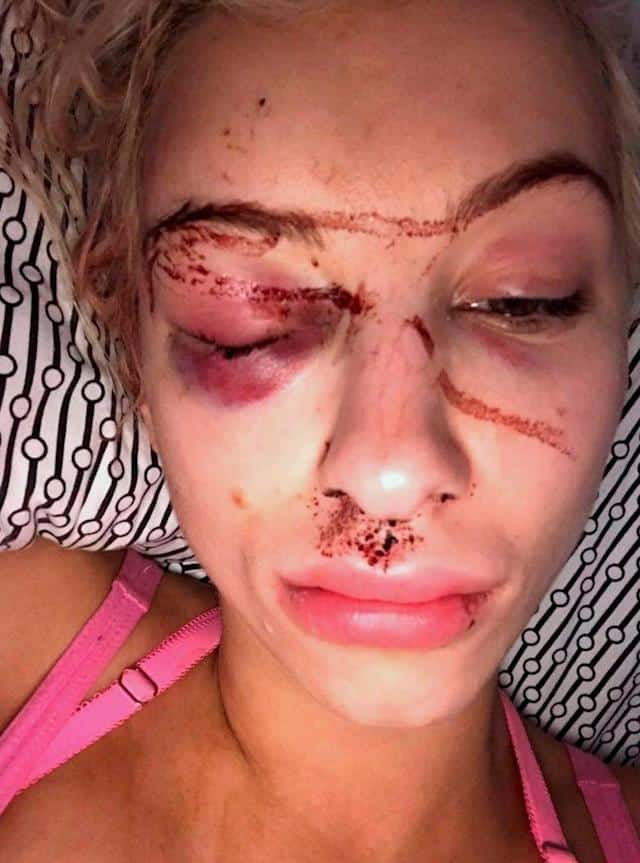

Τα τραύματα της Dolak περιελάμβαναν κάταγμα κρανίου, αιμορραγία στον εγκέφαλο και μόνιμη βλάβη σε ένα οπτικό νεύρο. Αλλά ανακάλυψε στην αυτοψία ότι ο εγκέφαλός της ήταν παρόμοιος με αυτούς τους ασθενείς με Αλτσχάιμερ και συμβατός «σε ένα βαθμό» με μποξέρ που έπασχαν από χρόνια τραυματική εγκεφαλοπάθεια και η υπόθεση έγινε η πρώτη σύνδεση στη βιβλιογραφία μεταξύ νευρογεννητικής νόσου και κακοποιημένων γυναικών.

Περίπου το 68% των θυμάτων βίας οικείου συντρόφου IPV βιώνουν σχεδόν στραγγαλισμό, αλλά μόνο τα μισά έχουν ορατά σημάδια τραύματος με μόνο το 15% αυτών που παρουσιάζουν ενδείξεις τραυματισμών στη συνέχεια να φωτογραφηθούν για να τεκμηριώσουν την κακοποίηση, σύμφωνα με το Ινστιτούτο.

Τα κοινά σημάδια στραγγαλισμού περιλαμβάνουν πετέχειες (μικρές κόκκινες κηλίδες που προκαλούνται από αιμορραγία κάτω από το δέρμα) στο πρόσωπο, στους βολβούς των ματιών και στα βλέφαρα, πρήξιμο, γρατσουνιές και εκδορές γύρω από το λαιμό, σύμφωνα με ένα ενημερωτικό δελτίο Στραγγαλισμόύ στη βία στενού συντρόφου.Strangulation in Intimate Partner Violence.

Οι Times συγκρίνουν τις σοβαρές εγκεφαλικές βλάβες με ισχυρούς σεισμούς, αλλά αντί να γκρεμίζονται γέφυρες και κτίρια, τα οστά μας σπάνε καθώς αργότερα εκρήγνυνται αιμορραγίες με ακατέργαστα επώδυνα τραύματα στο πρόσωπο.